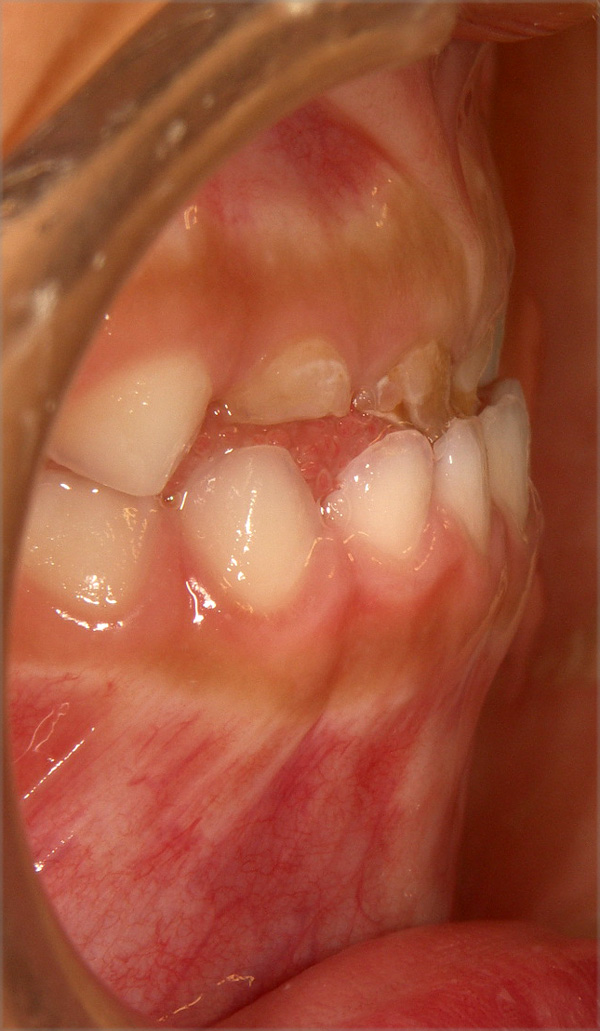

使用例: 乳犬歯が正常な咬み合わせである軽症例ですが、お父さんが骨格性反対咬合。

| 初診時4歳1ヶ月 装置使用2007.6.18〜2007.11.30 |

初診日2007.4.27 |